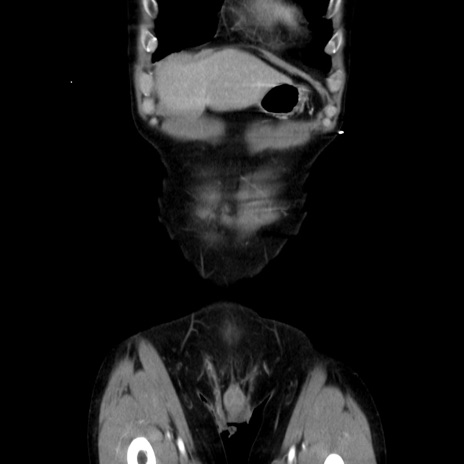

症例37(冠状断像)

【症例】40歳代 男性

【主訴】腹痛

【現病歴】4時間ほど前に電車に乗車中に臍部上より腹痛出現。徐々に増悪し起立困難となり、救急外来受診。生ものは数日食べていない。今朝お雑煮を食べた。

【身体所見】BT 36.8℃、BP 117/84mmHg、HR 91/min、SpO2 97%、苦悶様、腹部:臍上部広範囲圧痛あり、反跳痛±

【データ】WBC 8100、CRP 0.03